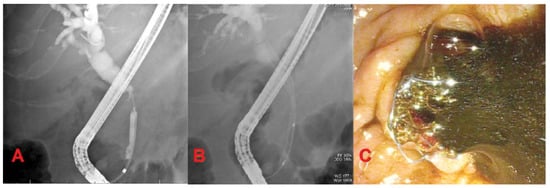

3.4. Endobiliary Radiofrequency Ablation (RFA)